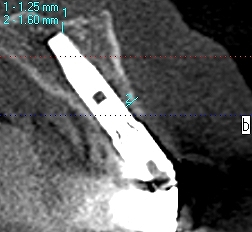

2番部はこのようにインプラントを適正な位置に即時埋入しています